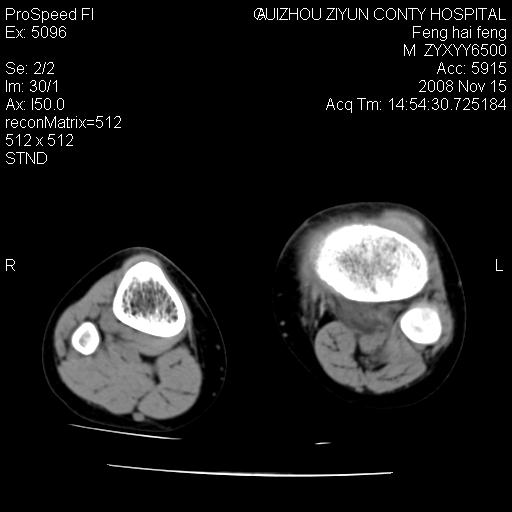

标题: CT16656:M 14Y 左膝关节肿胀一年余。其余病史不详。 [打印本页]

标题: CT16656:M 14Y 左膝关节肿胀一年余。其余病史不详。

考虑左侧髌骨结核;左膝关节滑膜肿胀、增厚,关节囊积液。

左膝滑膜型关节结核可能性大!支持!滑膜型关节结核主要ct表现:关节囊肿胀,积液,关节面见小破坏灶,并见点状死骨!

好大的左腿!考虑左侧髌骨结核,左膝关节滑膜肿胀、增厚,关节囊积液。

左侧髌骨结核;左膝关节滑膜肿胀、增厚,关节囊积液